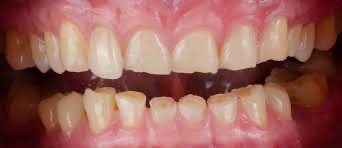

1️⃣ 牙齒會越磨越薄,變敏感、變脆

長期磨牙會讓牙齒磨耗、變平,

甚至刷牙都會覺得酸、痛。